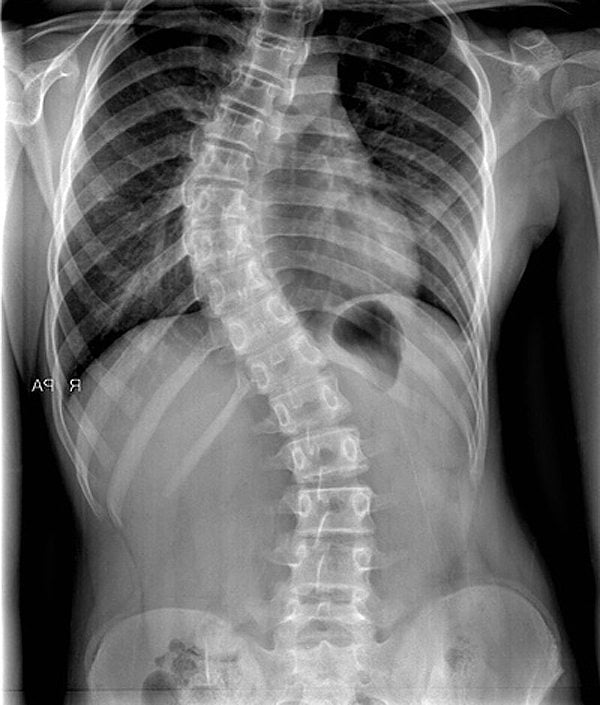

Сколиозом называется стойкая трехплоскостная деформация позвоночника врожденного, приобретенного или посттравматического происхождения. Наблюдается его искривление в боковой плоскости. Затем происходит скручивание позвонков, усиливающее физиологические изгибы позвоночника.

Сколиозы бывают структурными и неструктурными. Для последних характерна менее выраженная деформация — отмечается боковое искривление без стойкого скручивания позвонков. Патология также классифицируется в зависимости от направления искривления позвоночного столба.

У пациентов с жалобами на дискомфортные ощущения в одном из отделов позвоночника в большинстве случаев выявляется правосторонний сколиоз. Он диагностируется примерно у 70% больных. Из-за смещения позвоночного столба вправо расстраивается функционирование внутренних органов, особенно сердечно-сосудистой и дыхательной систем.

Левосторонний сколиоз диагностируется значительно реже, чем правосторонний. Наиболее часто патология преимущественно грудной локализации обнаруживается у женщин. Из-за бессимптомного течения левосторонний сколиоз обычно выявляется случайно при проведении инструментальной диагностики других заболеваний, например, остеохондроза.

Помимо внешнего осмотра пациента, результатов ряда функциональных тестов, в диагностике сколиоза наиболее информативна рентгенография. Сначала исследование проводится в положении стоя, затем — лежа при умеренном растягивании для более детальной оценки искривления позвоночника.

Рассчитать угол сколиотической дуги помогает методика, разработанная Коббом. Сначала на рентгенографическое изображение, сделанное в прямой проекции, наносятся две линии параллельно замыкательным пластинкам здоровых позвонков, а потом измеряется угол между ними.